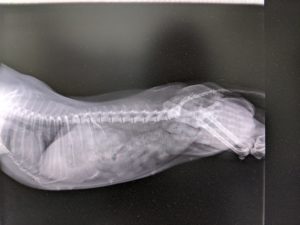

つばちゃん、お腹に1頭はいるように思ったので、今朝、レントゲン検査に行きました。

今回のレントゲン検査

体重3.6 kg

前回のレントゲン検査

体重3.3kg

今回は残念、カラでした…

妊娠してる割にはお腹、乳のハリが弱いですし、陰部も緩い感じでしたが、お産するような感じではありませんでしたが…熱はお産前の体温の変化はありましたが、最近気温差も激しいですしね。胎児の動きに思っていたのは、筋肉だったのかもしれないですね。今、思うと、つばちゃんのお腹ジーとずっと見てましたから!!笑。つばちゃん緊張したり、まだ?とか思いながら頑張ってくれてたんでしようね。m(__)m